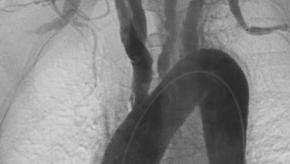

Read ArticleNoninfectious Proximal Aortitis Needs Serial Follow-ups

A Cleveland Clinic review of patients undergoing thoracic aortic surgery (1996‐2012) identified 196 patients with histopathology‐proven non‐infectious aortitis.